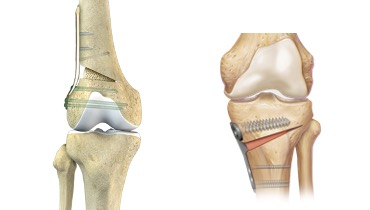

- Artroscopia: cirurgia minimamente invasiva, feita com câmera. Serve para “limpar” o joelho e tratar lesões associadas, mas não resolve artrose avançada. É como tirar sujeira de dentro de uma engrenagem.

- Osteotomia: corrige o alinhamento do joelho, redistribuindo o peso. É como alinhar um carro para evitar desgaste irregular do pneu.

- Prótese de joelho: substitui a articulação desgastada por uma artificial.